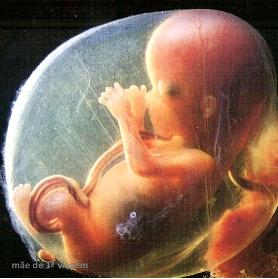

12 Semanas de Gestação

Sua 12a semana começa

- Desenvolvimento Seus cabelos surgem como penugem e sua genitália começa a ficar mais definida.

- O desenvolvimento do bebê com 12 semanas de gestação está a todo vapor. Seus pequenos dedos das mãos e dos pés começam a se formar, assim como suas unhas.

- O feto se mexe sem parar e parece estar em um parque de diversões onde vira para um lado e para o outro, nadando sem parar.

- Nas 12 semanas de gravidez, a aparência da sua cabeça, antes tão desproporcional ao restante do corpo, pausa seu crescimento um pouco o crescimento.

O desenvolvimento fetal na 12ª semanas de gestação está a todo vapor. Seus pequenos dedos das mãos e dos pés começam a se formar, assim como suas unhas. Seu cabelo começa a aparecer como uma suave penugem. Nesta semana ele chega a medir em torno de 5,4 cm da cabeça ao bumbum e pesa em média 58 gramas.

O órgão genital está cada vez mais bem formado1 e ficando cada vez mais nítido para ser visto através do exame de ultrassonografia. O feto se mexe sem parar e parece estar em um parque de diversões onde vira para um lado e para o outro, nadando sem parar. Com muita sorte, esses movimentos podem ser assistidos durante a ultrassonografia!

Nas 12 semanas de gravidez, a aparência da sua cabeça, antes tão desproporcional ao restante do corpo, pausa um pouco o crescimento. Neste momento seu corpo começa a ganhar peso e cada dia fica mais parecido com o bebezinho que chegará ao mundo.